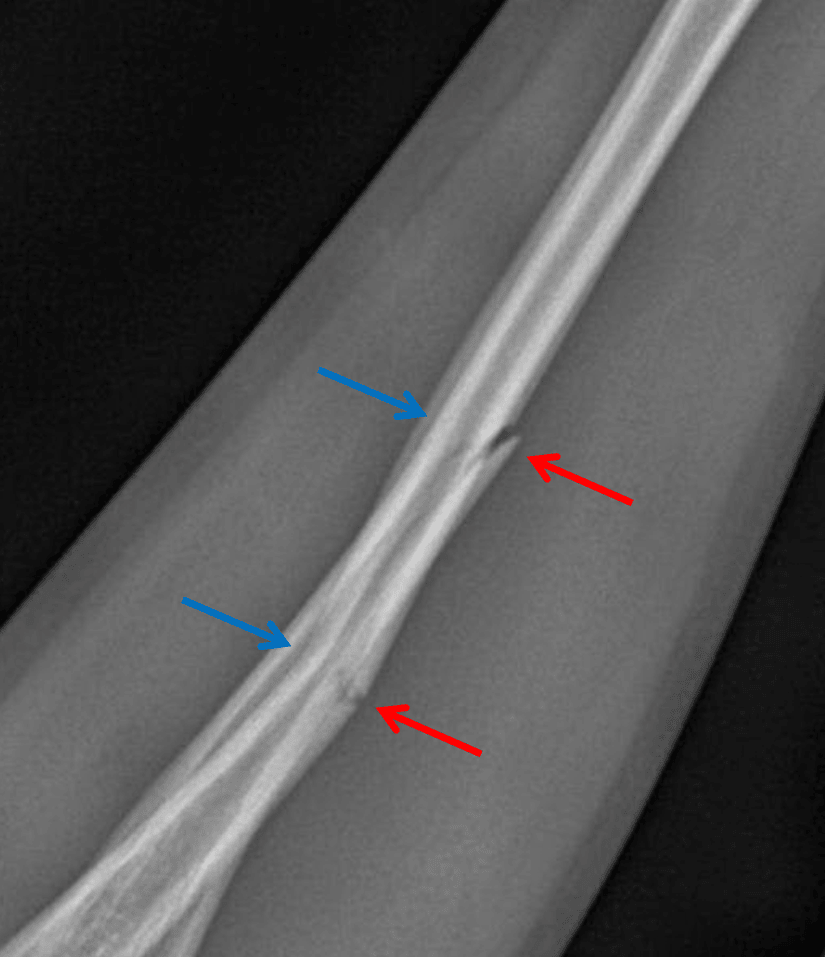

Acute greenstick fractures of the mid radial and ulnar diaphyses with apex volar angulation.

Greenstick Fracture - Red arrows: disrupted cortex. Blue arrows: intact opposite cortex.